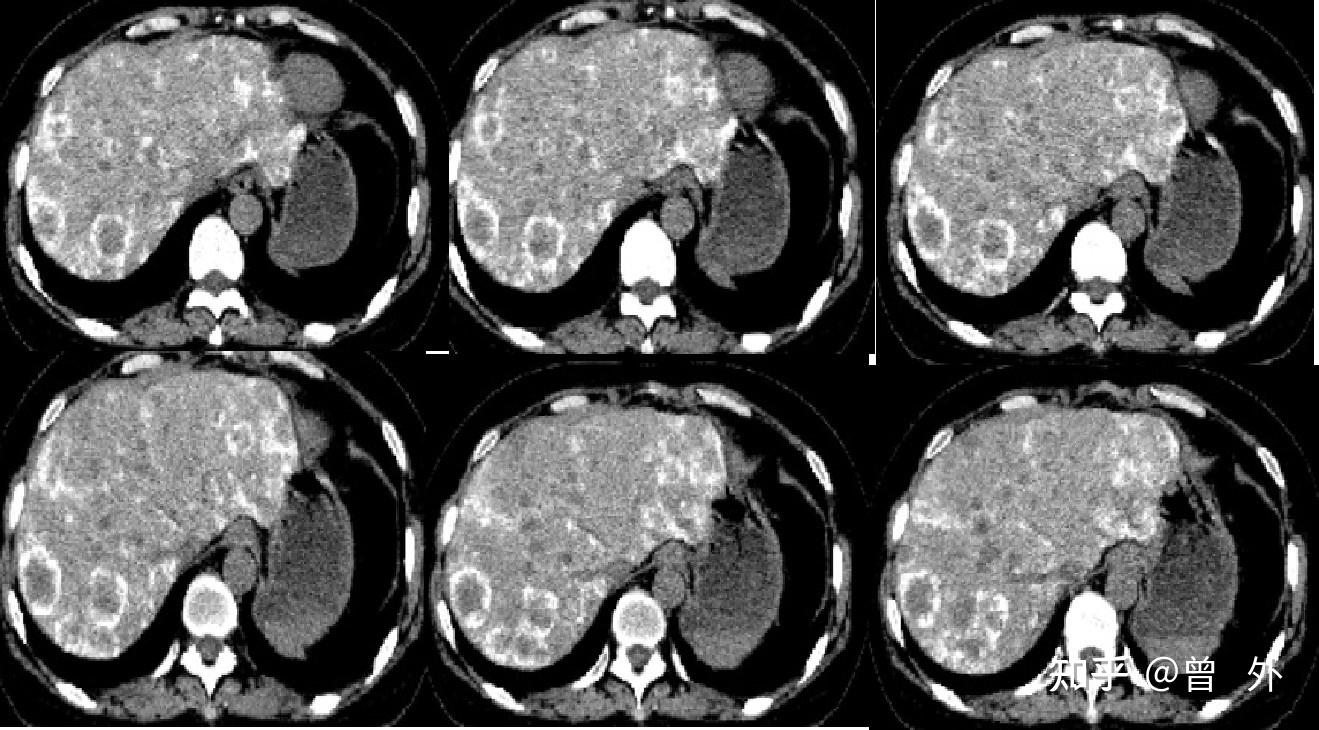

【病例分享】直肠癌多发肝转移:病理完全缓解一例

图片尺寸726x529